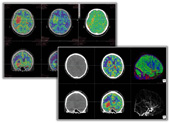

■4D Brain Analysis

「4D Brain Analysis」(WIP)ではエリアディテクタCT(ADCT)から得られる2万枚以上の頭部データを高速処理し,脳の血流と機能の画像を同時に表示することで視覚的な評価を実現しました。

4D Brain Analysis

【画像クリックで拡大表示します 】